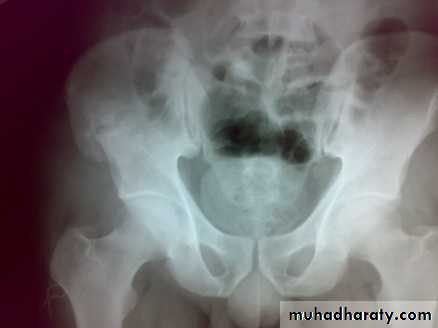

Fracture pubic ramai

Fracture pubic rami